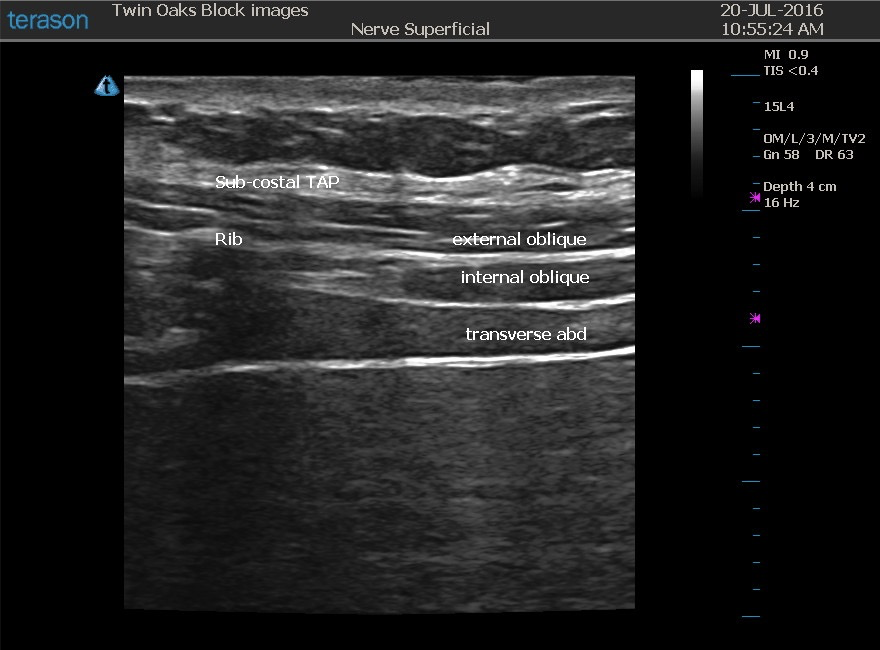

From www.twinoaksanesthesia.com

TAP Block — CRNA Conferences Twin Oaks Anesthesia Tap Block Local Anesthetic Volume the transversus abdominis plane (tap) block is a fascial plane block performed by injecting local anesthetic in. a large volume of local anesthetics is required to hydrodissect the tap along the whole ipsilateral oblique. this peripheral nerve block is performed with the goal of depositing local anesthetic in the neurovascular “interfascial” plane. depending on the patient’s. Tap Block Local Anesthetic Volume.